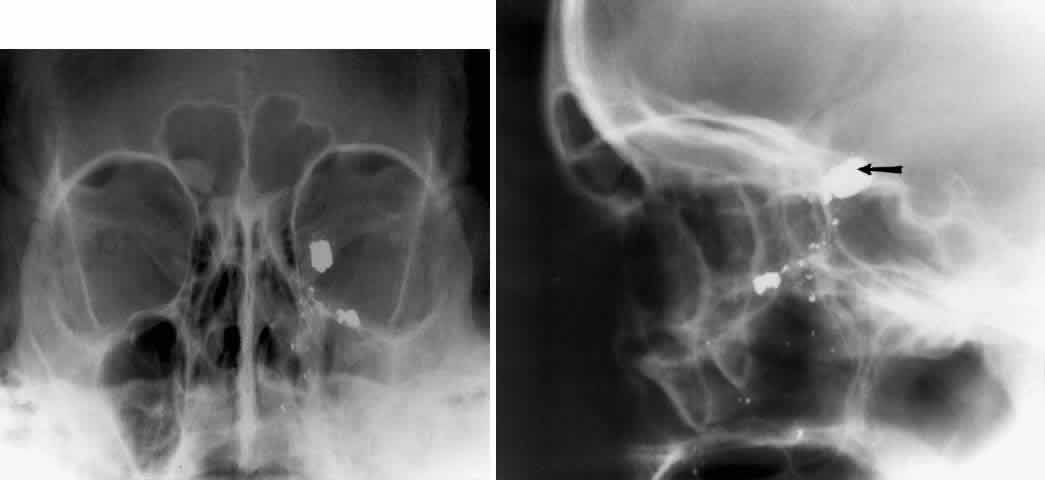

The orbital floor consists of the maxillary, zygomatic, and palatine bones. The floor is thinnest medial to the infraorbital canal, which is the location of most orbital floor fractures (Fig. 7). As mentioned earlier, the floor slopes upward from the lateral to the medial wall. The floor extends toward the orbital apex but does not reach the apex. This orientation of the floor makes frontal projections more informative than the lateral projection.

Fig. 7. A patient involved in a motor vehicle accident who sustained a right orbital floor fracture. Soft tissue density (arrow) located in the roof of the maxillary sinus. Disruption of the orbital floor is seen at the fracture site.

Waters view gives the best image of the anterior and middle portion of the floor. This is possible because extension of the neck brings the floor into a position that is tangential to the x-ray beam. The floor is represented by the most inferior radiopaque line, whereas the orbital rim will be the line above it.10 The vertical distance between these lines should be approximately 1 cm.19 This relationship between the floor and the orbital rim should be symmetric between the two orbits. Any asymmetry should suggest a fracture of the orbital rim or floor.